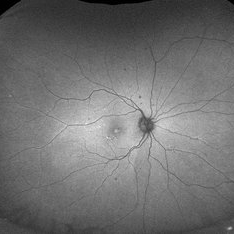

Oculocutaneous Albinism

Jan 14 2024 by Hemanth Murthy, MBBS, MD, FASRS

9 year boy presented with pendular nystagmus and blurring of vision. He light skin colour with light coloured hair. Fundus picture of right eye

Photographer: Mr Veda Vyas

Imaging device: Optos Daytona

Condition/keywords: albinism